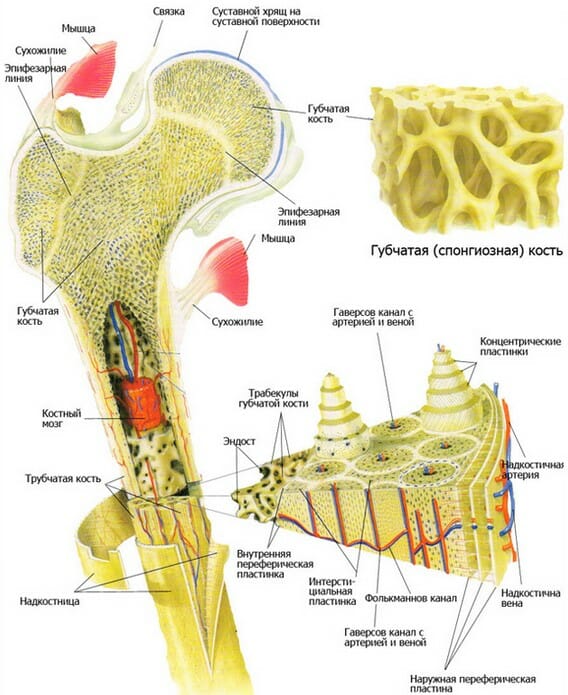

Изучение костного мозга: анатомия и функции